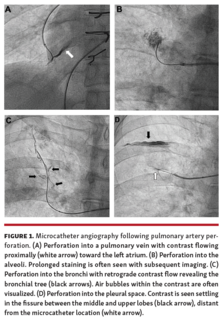

Zachary L. Steinberg, MD; William L. Lombardi, MD; Joshua S. Lee, MD, DO; Michael S. Mulligan, MD; Peter J. Leary, MD, PhD

This study is a retrospective case series of all BPAs on CTOs for individuals with CTEPH at a single institution. Procedural approach, complications, and success rate over a 6-month period are described.